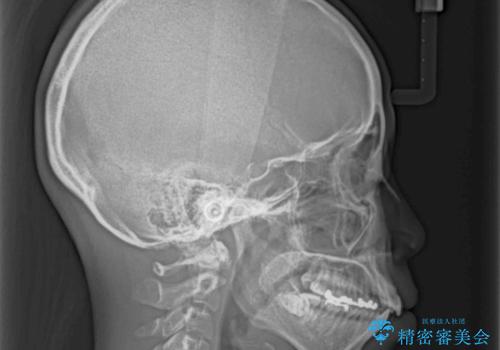

- 上の前歯の捻じれと突出感を気にして来院された患者様です。

目立たない装置を希望とのことで、上顎左右第一小臼歯を抜歯し、インビザラインにて矯正治療を行うこととしました。